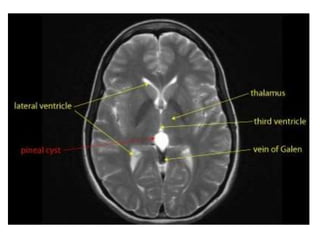

1-Benign Cyst :

a) Incidence

a) Incidence :

20-30 years of age, more in women

-Simple cystic structure within the gland

measuring < 1.5 cm

-Unlikely to be significant when no mass effect

and when there are no relevant symptoms

b) Radiographic Features :